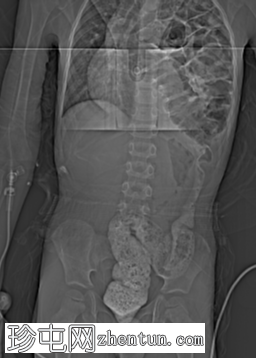

荧光透视

正面

消化道造影检查显示食管口径正常,胃明显延长,延伸至盆腔区域。

左胸腔可见囊性透亮区,与腹部相连,导致心脏轮廓向右侧移位。